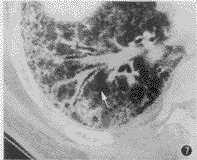

图7 慢性支气管炎合并间质纤维化。支气管血管束增粗、边缘毛糙

支气管血管束增粗、边缘毛糙、扭曲变形多见于肺间质纤维化。本组影像与病理对照表明,支气管血管束异常不只是支气管血管周围结缔组织病变,而主要反映了其周围肺组织病理变化。

在肺间质性炎性病变,支气管血管束异常表现主要为边缘改变,包括边缘模糊、毛糙、不规则等,仅根据这些改变,不能区别支气管血管周围间质纤维化与其周围肺实质炎症,二者鉴别需结合CT其他征象。支气管血管束走行异常,如支气管血管束扭曲变形、走行僵直,反映了支气管血管周围肺组织纤维化及肺结构破坏,是周围肺组织牵拉的结果。本组慢性支气管炎合并间质纤维化的病例中,边缘毛糙占56%,扭曲变形占40%。虽然支气管血管束异常为肺间质纤维化的常见表现,但并不是诊断的主要依据,肺间质纤维化的诊断必须结合肺周围间质改变的征象,如小叶间隔增厚、小叶内间质增厚等。